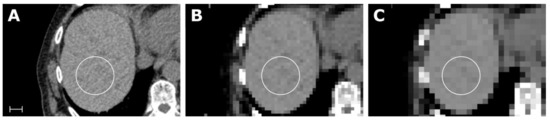

2.1. Concept of the Parametric Map Creation Tool

4.2. Parametric Map Resolution/VOI Size